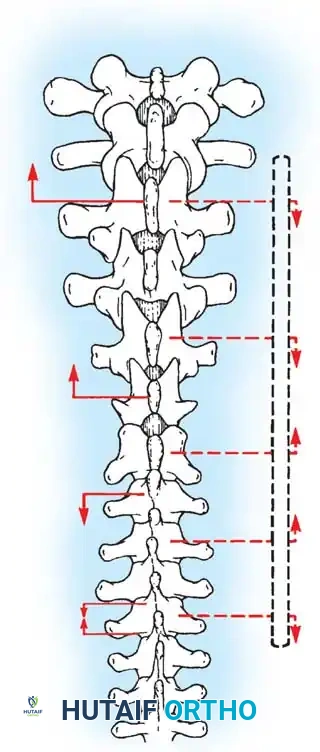

Fig. 38-23: A, Skin incisions for posterior fusion. B, Incisions over spinous processes and interspinous ligaments. C, Weitlaner retractors maintaining tension during dissection.

- Incision Planning: Make a straight midline skin incision extending from one to two vertebrae superior to the proposed upper instrumented vertebra (UIV) down to one vertebra inferior to the lower instrumented vertebra (LIV). A perfectly straight scar significantly improves the postoperative cosmetic appearance.